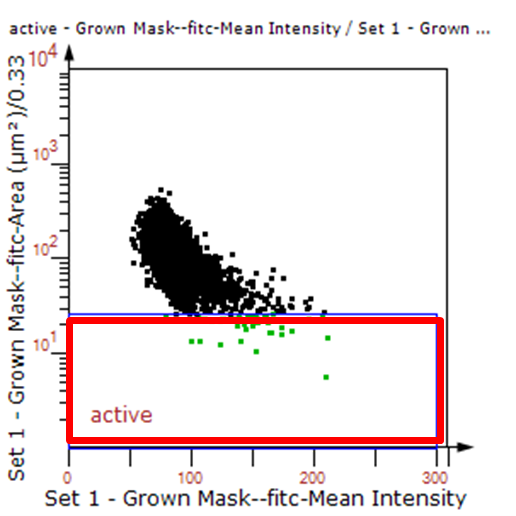

由于该视网膜样本是标记的小胶质细胞,根据面积将神经胞体分为两类(Small bodycell,Big bodycell),反向回溯Big bodycell中的细胞后,应用Input Gate功能筛选短粗的神经纤维,作为激活态的小胶质细胞。

激活态小胶质细胞识别

血管与小胶质细胞的距离0-0.1μm(红色框线标记)

血管与小胶质细胞的距离0.1-1μm(粉色标记)

血管与小胶质细胞的距离1-3μm(粉色标记)